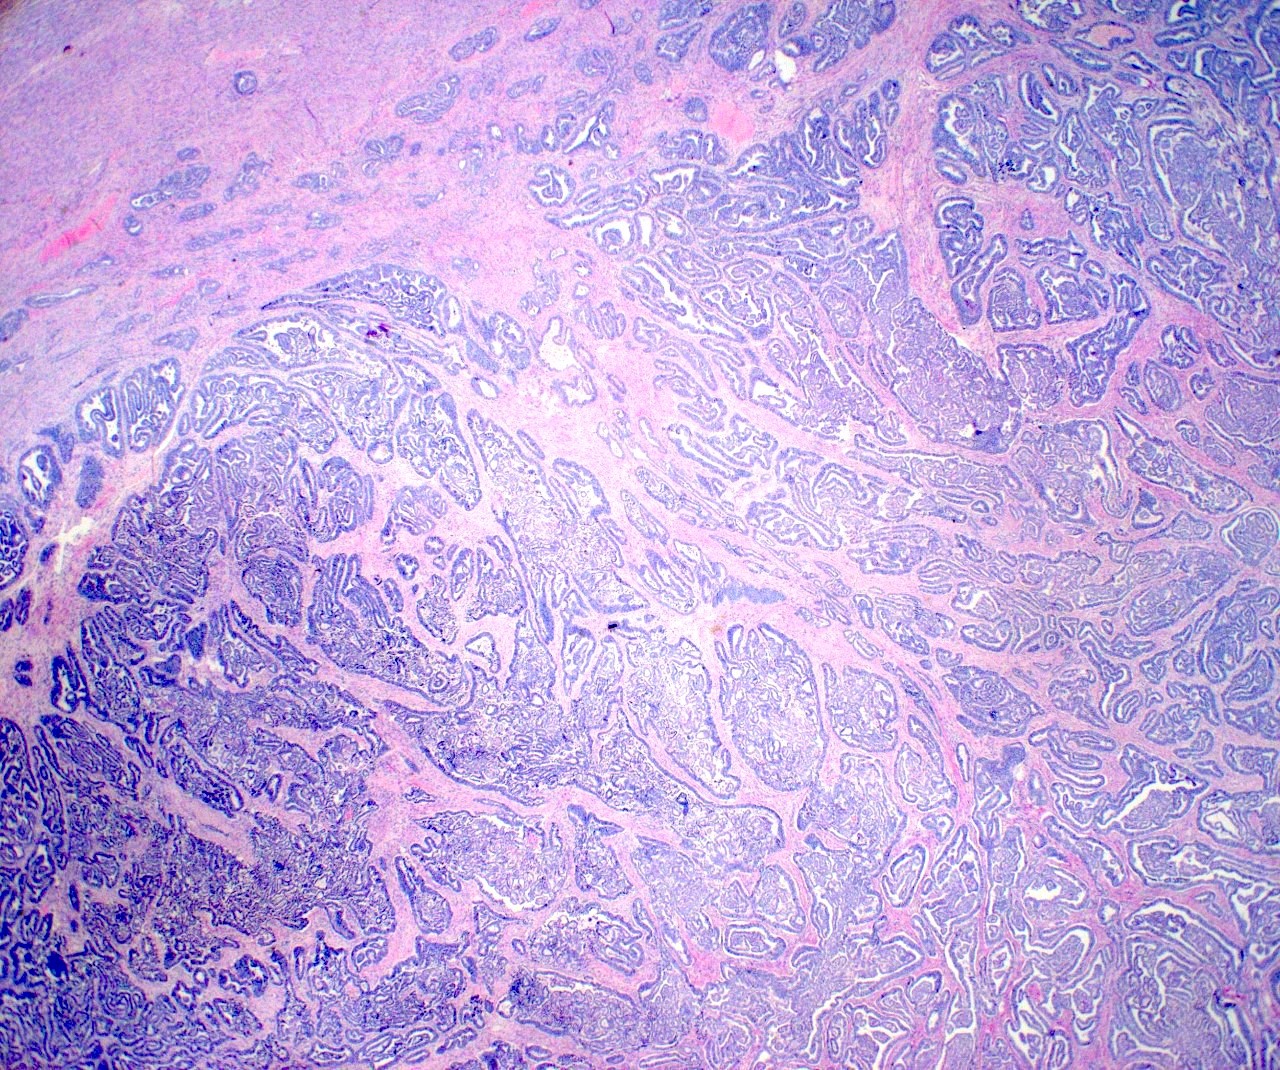

- Variety of histologic patterns that may be present within the same tumor

- Most frequently small tubules with ductal / glandular growth

- Papillary, solid growth, trabecular, retiform, sex cord-like, sieve-like, glomeruloid and spindle cell areas have all been described

- Luminal eosinophilic secretions are characteristic but not always identified

- Tumor cells can be flattened, cuboidal or columnar with mild to moderate cytological atypia

- Clear cell features can be seen but are less common

- High grade cytological atypia is usually not a predominant feature

- Nuclei show vesicular chromatin and nuclear grooves

- Sarcomatoid transformation has been seen in rare instances

- Squamous, ciliated or mucinous differentiation (metaplasia) are not present and there are no associated mesonephric remnants (J Clin Med 2021;10:698)

Microscopic (histologic) images

Contributed by Daniel Graham, M.D., Adele Wong, M.B., B.Ch., B.A.O. and Lucy Ma, M.D.